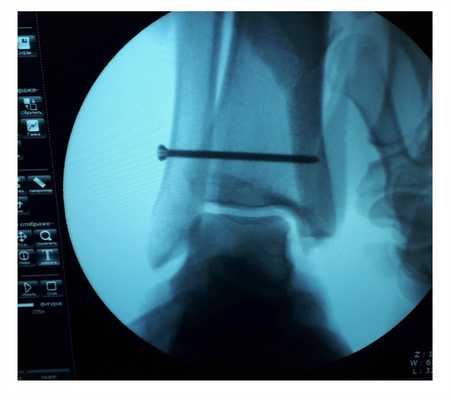

Ниже представлены этапы оперативного лечения.

После восстановления латерального связочного комплекса по Брострому в модификации Голда и фиксации межберцового синдесмоза винтом производится оценка стабильности голеностопного сустава при помощи вальгус—стресс теста под контролем ЭОП.

Через 6 недель производится удаление позиционного винта. С этого момента разрешается полная осевая нагрузка.

На рентгенограммах видно что после удаления позиционного винта взаимоотношения большеберцовой и малоберцовой костей остаётся прежним, что свидетельствует в пользу того что лечение прошло успешно.